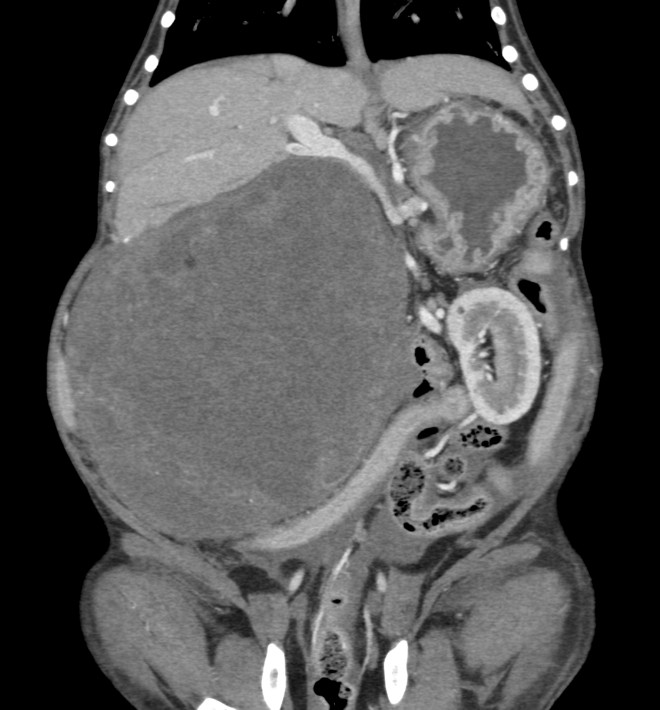

今回治療させていただいたワンちゃんは、ここ1年ほどでお腹が張ってきており、散歩中に立てなくなったとの事で来院されました。原因は、巨大な脾臓腫瘍と、脾臓腫瘍から壊死物質が漏れたことによる腹膜炎でした。重度の貧血を呈していたため、輸血で状態を安定化し、翌日に手術を行いました。脾臓腫瘍は、直径20センチ、重さ2.7kgで、病理組織学的検査は「脂肪肉腫」でした。幸いなことに、手術前のCT検査で転移所見はありませんでした。